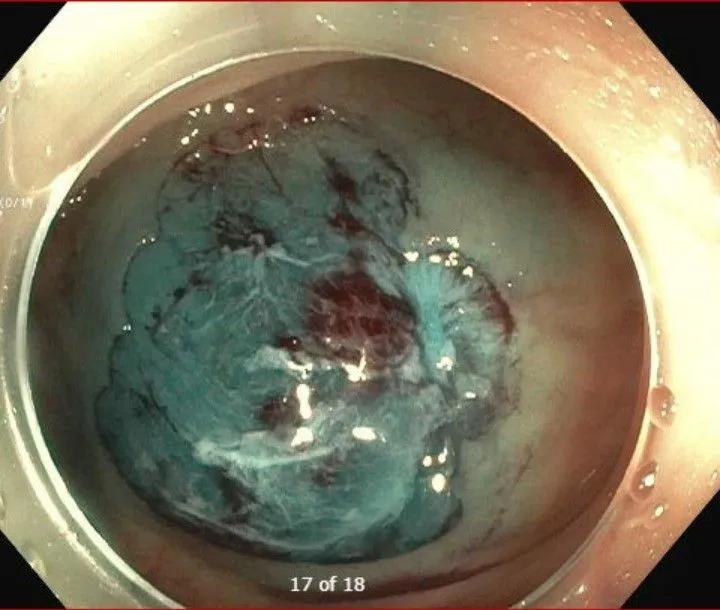

Cold EMR (After)

Endoscopic mucosal resection (EMR) is the standard of care for many benign colorectal lesions, offering patients a less invasive alternative to surgery. However, conventional hot EMR carries a well-recognized risk of adverse events, including delayed bleeding and perforation – complications that remain a source of concern, particularly for large polyps.

Cold EMR, which avoids electrocautery, has emerged as a compelling safety-focused alternative. Once limited to smaller lesions, it is increasingly being applied to larger and more complex polyps as experience and technique evolve. At Cleveland Clinic Weston Hospital, the interventional endoscopy team led by Tolga Erim, DO, is helping define the expanding role of cold EMR through high-volume clinical practice, education, and research.

Cold EMR involves submucosal injection to lift a lesion followed by snare resection without electrocautery. Historically, cold techniques were limited to polyps smaller than 10 mm. Advances in technique and operator experience have expanded its use to larger lesions, although cold EMR remains an advanced approach not yet widely available.

The primary advantage of cold EMR is its safety profile. By eliminating thermal injury, the technique substantially reduces the risks of delayed bleeding and perforation, two of the most concerning complications of endoscopic resection.